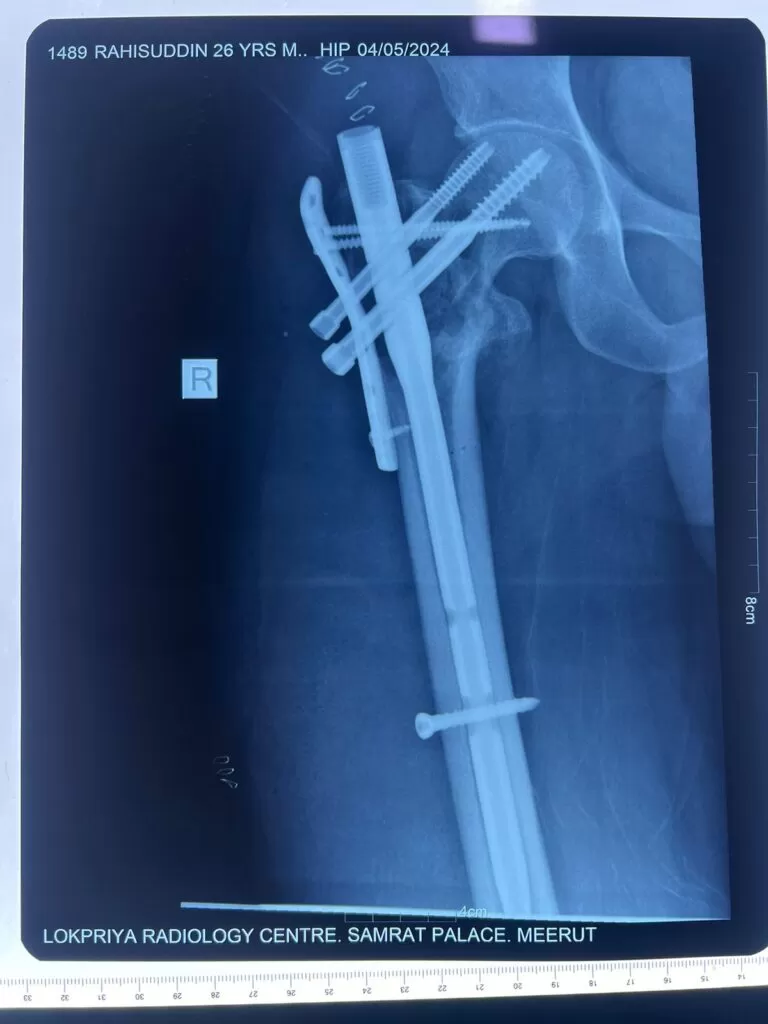

Mr. Rahisuddin

Name: Mr. Rahisuddin

Date of Operation: 04 May 2024

Age: 25 Years